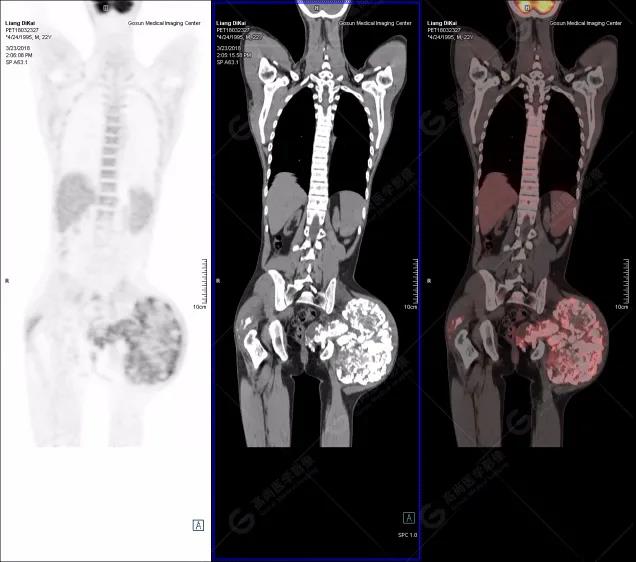

1.右肘關(guān)節(jié)周圍、骶尾部皮下、雙側(cè)臀部、盆腔左側(cè)壁及左側(cè)大腿根部肌肉、肌間隙多發(fā)結(jié)節(jié)狀、片塊狀及不規(guī)則巨塊狀高密度鈣化灶,伴代謝不均勻輕度增高,考慮為鈣質(zhì)沉著癥;

鈣質(zhì)沉著癥:是不溶性鈣鹽沉積于組織所產(chǎn)生的疾病。分為特發(fā)性、轉(zhuǎn)移性和營養(yǎng)不良性。特發(fā)性鈣質(zhì)沉著癥多原因不明,轉(zhuǎn)移性鈣質(zhì)沉著癥繼發(fā)于鈣磷代謝障礙性疾病,如甲狀旁腺功能亢進、多發(fā)性骨髓瘤、腎功能不全使磷酸鹽潴留等,本例病例既為甲狀旁腺功能亢進引發(fā)鈣質(zhì)沉著典型表現(xiàn)。